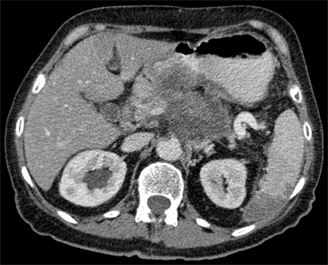

This slide show features a CT image, and pathology images of gastrointestinal stromal tumors (GISTs) arising in the stomach using H&E, CD34, and c-Kit staining.